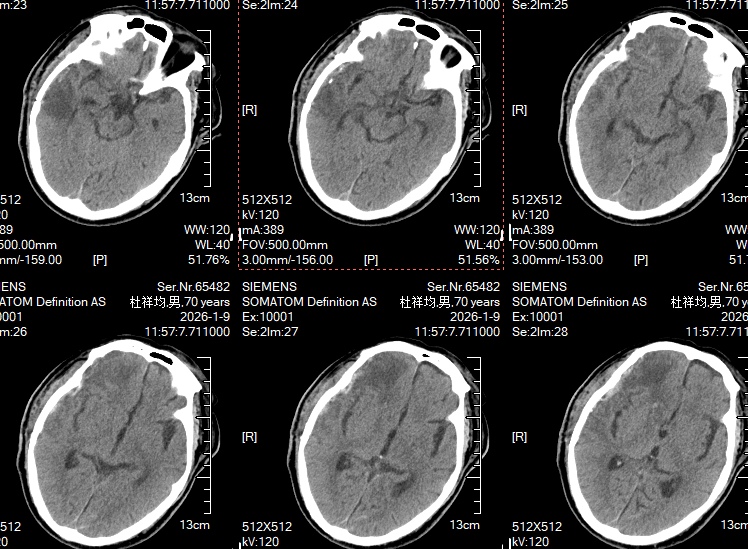

术后两周复查头颅CT:血肿完全清除